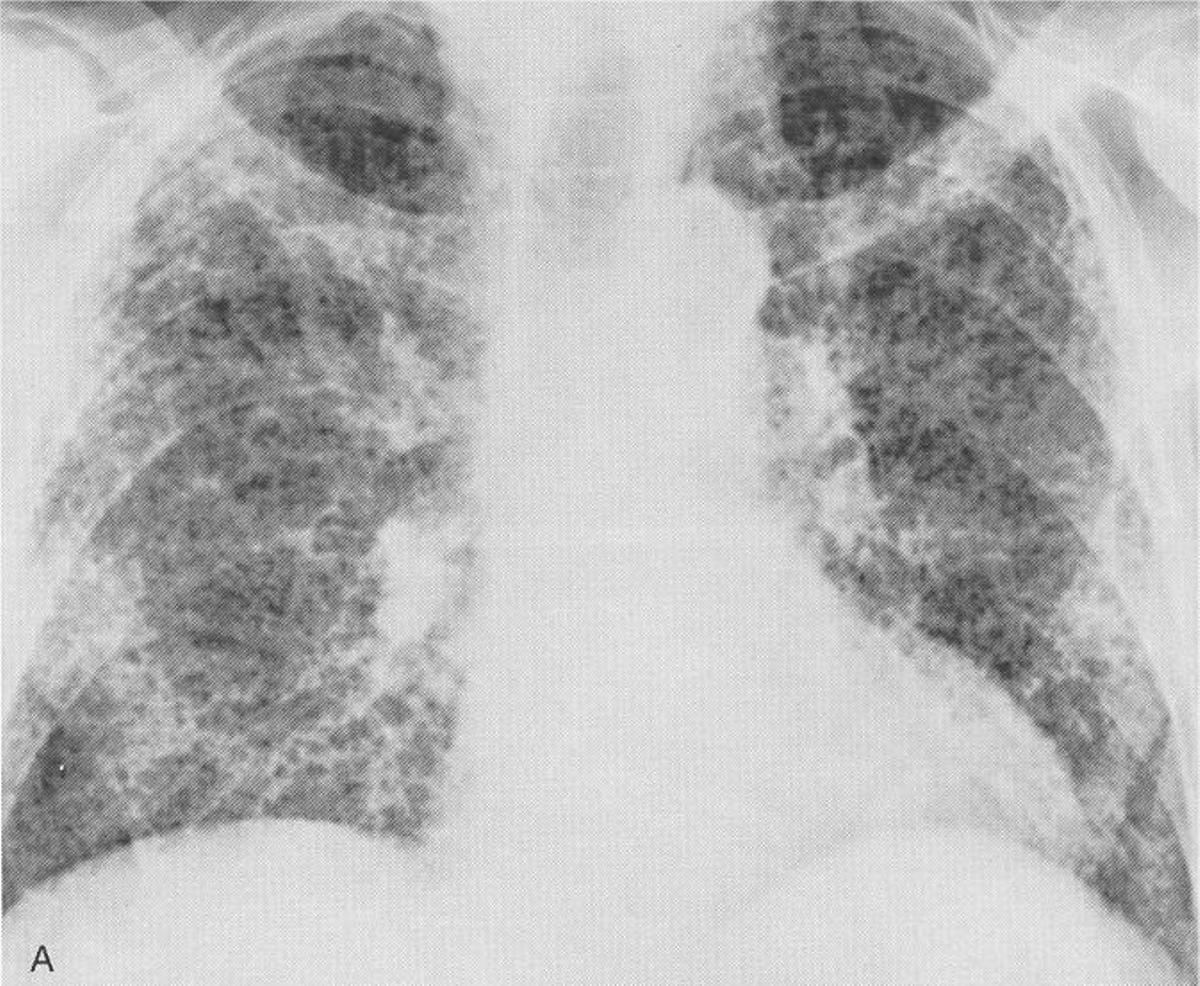

Una radiografía de unos pulmones.